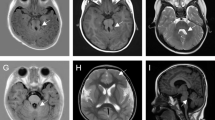

Chromosome analysis in peripheral lymphocytes showed a normal male karyotype (46,XY) at a banding resolution of 400 bands per haploid genome. Whole exome sequencing analysis was performed on the patient, a large heterozygous copy number deletion on CREBBP gene, from exon 29 to exon 31 (chr16 3778026-3781885) was identified on the patient, this mutation was de novo and not found on his parents by sanger sequencing (Fig. 3). We used long PCR and Sanger sequencing to determine the location of the breakpoint on the patient, and found that the upstream breakpoint position of the heterozygous copy number deletion is chr16:3745392, and the downstream breakpoint position is chr16:3783895. It is confirmed that the size of the heterozygous copy number deletion is 38503 bp, and a sequence of nearly 300 bp has been inserted at the breakpoint. It might be caused when DNA double-strand break damage is repaired (Fig. 3). This heterozygous copy number deletion region chr16:3745393-3783894 covers the exon 1 region and part of the intron 1 region of the TRAP1 gene, and the entire region from intron 27 to exon 30 of the CREBBP gene. In general, this pathogenic heterozygous deletion is the causative mutation for the disease phenotype in this family.

Pedigree of affected family (A). Whole exome sequencing analysis identified a large heterozygous copy number deletion on CREBBP gene, from exon 29 to exon 31 (chr16 3778026-3781885) on the patient, this mutation was de novo and not found on his parents by sanger sequencing (B). Long PCR and Sanger sequencing showed that the heterozygous copy number deletion region chr16:3745393-3783894 covers the exon 1 region and part of the intron 1 region of the TRAP1 gene, and the entire region from intron 27 to exon 30 of the CREBBP gene (C, D)